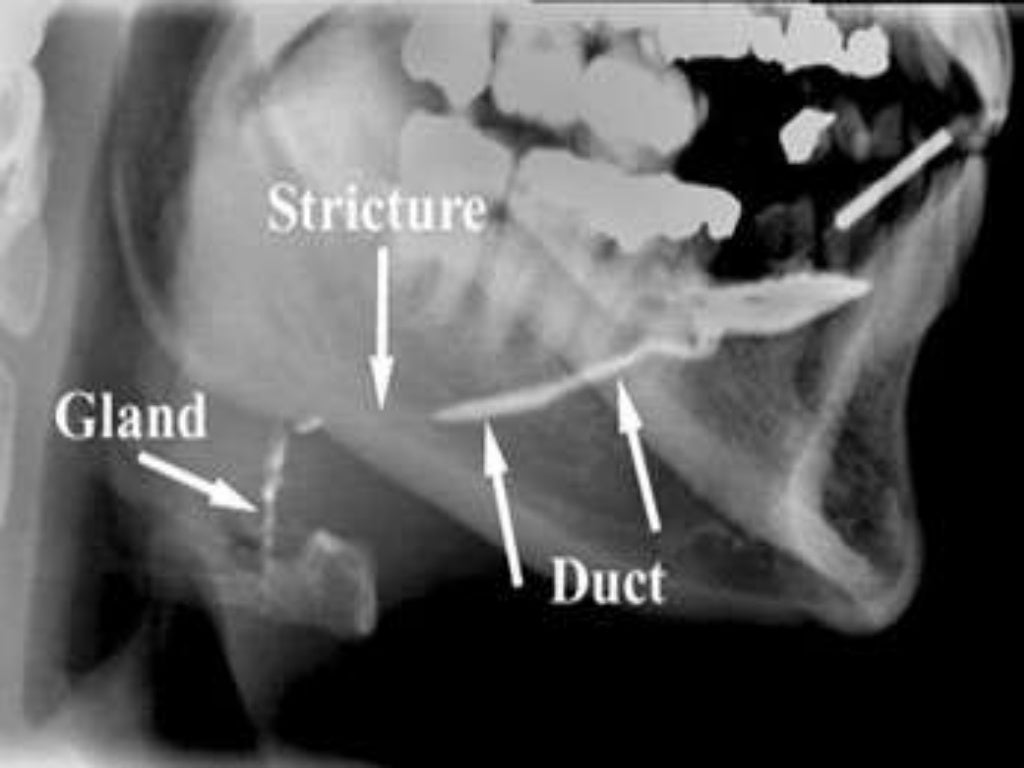

PPT Sialography PowerPoint Presentation, free download ID4581600 Radiopaque Salivary Calculi A radiographic and histologic study salivary calculi and chronic sialoadenitis of the submandibular gland: They are typically composed of calcium phosphate and hydroxyapatite, as the saliva is rich in calcium. sialography is the imaging of the salivary glands, most commonly the parotid gland. Stones will form in the salivary gland or ducts following the stagnation of saliva; . Radiopaque Salivary Calculi.